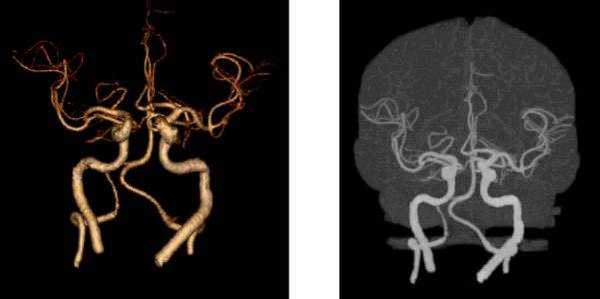

3D-изображения компьютерной мультиспиральной томографии Виллизиева круга. Его контуры можно увидеть на томограмме в центре, шея внизу, основные артерии белого цвета.